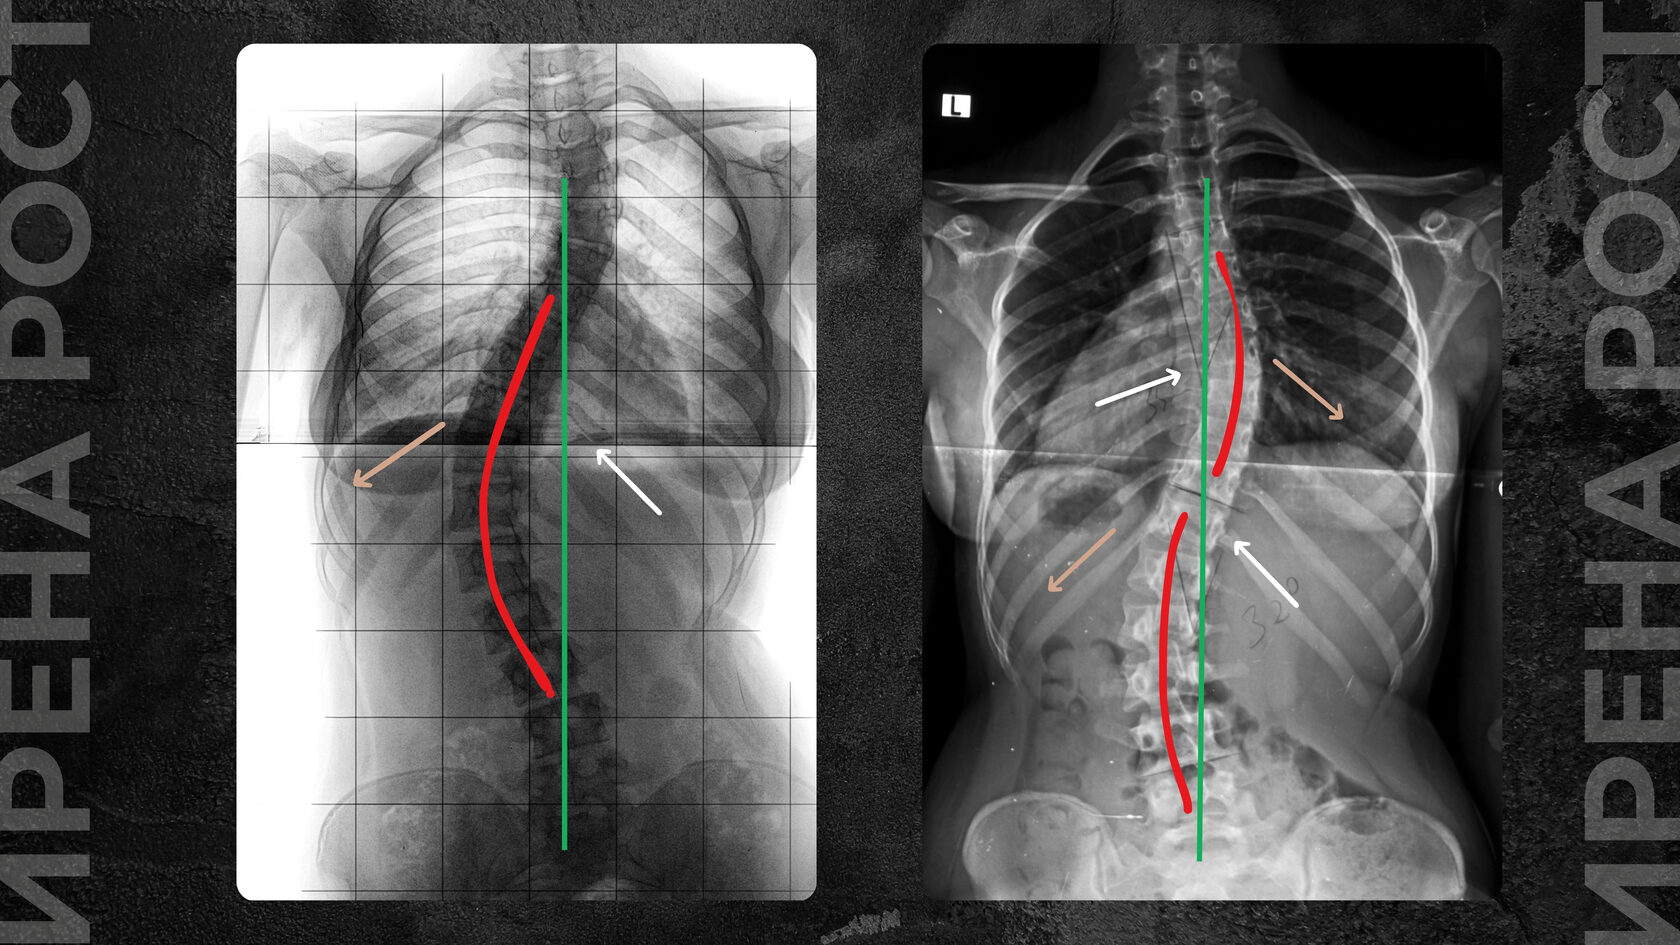

Реберный горб формируется при искривлении позвоночника в шейно-грудном, грудном или грудо-поясничном отделах, начиная со II степени искривления. Он появляется при вовлечении грудной клетки в сколиотическую дугу и ротацию (поворот) позвоночника. Сколиотическая дуга по мере ее увеличения, увеличения градусов отклонения позвоночника от вертикальной нормы, вовлекает в процесс и ребра, которые крепятся к позвонкам.

Так, со стороны сколиотической дуги ребра начинают сжиматься, создавая выпуклость полости грудной клетки, создавая реберное выпячивание (горб), а со стороны, противоположной дуге, ребра, наоборот, растягиваются, создавая сплющенность (впуклость) грудной клетки.